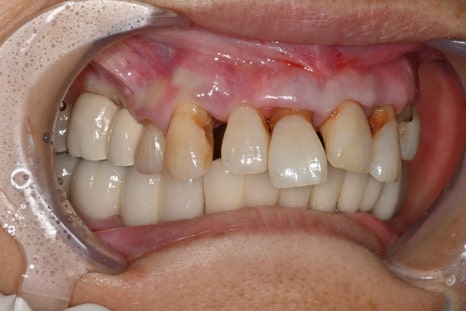

초진내원당시

이번 환자분은 65세 여성으로

위 앞니가 여러 개 상실된 상태로 내원하셨습니다.

앞니 상실은 단순히 치아가 없는 문제를 넘어서

웃을 때 보이는 심미 문제

발음의 변화

식사 불편

심미를 결정하는 보철 디자인

전치부 임플란트에서 가장 중요한 단계는

보철 디자인입니다.

이번 케이스에서도

맞춤형 어버트먼트 적용

임시 보철을 통한 형태 확인

최종 지르코니아 보철 제작

과정을 거쳐 완성되었습니다.

앞니는 단순히 하얀 치아가 아니라

✔ 자연스러운 색상

✔ 빛이 통과하는 투명도

✔ 잇몸과의 경계

가 모두 자연스러워야 합니다.

치료 후 변화

치료 후 환자분은을 경험하셨습니다. 특히

“내 치아처럼 자연스럽다”는 반응을 보이셨습니다.